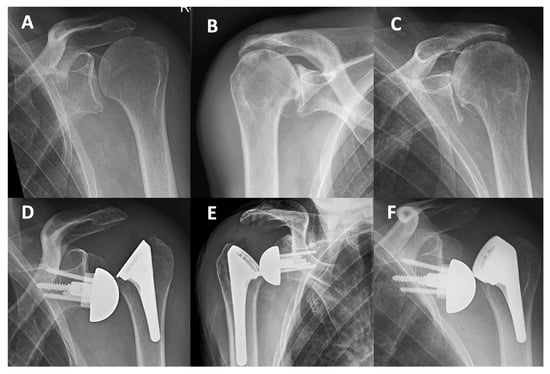

Figure 3. Preoperative radiographs of three patients who sustained dislocations (AC). Superior–lateral dislocations of short Perform stems in combination with standard non-retentive liners (DF).

The indication for RSA was CTA in two of these patients, and one had a massive cuff tear (Figure 3). In one of the four cases, the subscapularis had been repaired, was still intact at revision, and did not prevent superior–lateral instability. This first dislocation (case 1, Table 4) was revised to a +9 mm spacer with a +3 mm standard 10° 39 mm insert (LSR 147%) and dislocated again, requiring a second revision (case 2, Table 4). A varus alignment of 6° (effective NSA 129°) was considered to contribute to the superior–lateral instability (Figure 3D,F) and corrected (stem revision of case 2) and combined with +6 mm 10° standard liner +9 mm spacer (+15 mm in total). The glenosphere was changed from a 39 mm eccentric to a centered 42 mm implant. In summary, superior–lateral instability occurred in 8% of the cases with a standard non-retentive liner (4/50), LSR < 158%). Three liner-change revisions and a major revision involving both a liner, glenosphere and stem exchange to correct the varus alignment (129°) were necessary to achieve stability. The contributing factors affecting instability in the four adverse dislocation events were low LSR (four times), liner type (three times), MRCT or CTA (four times), varus alignment (one time), and low compression (one time).